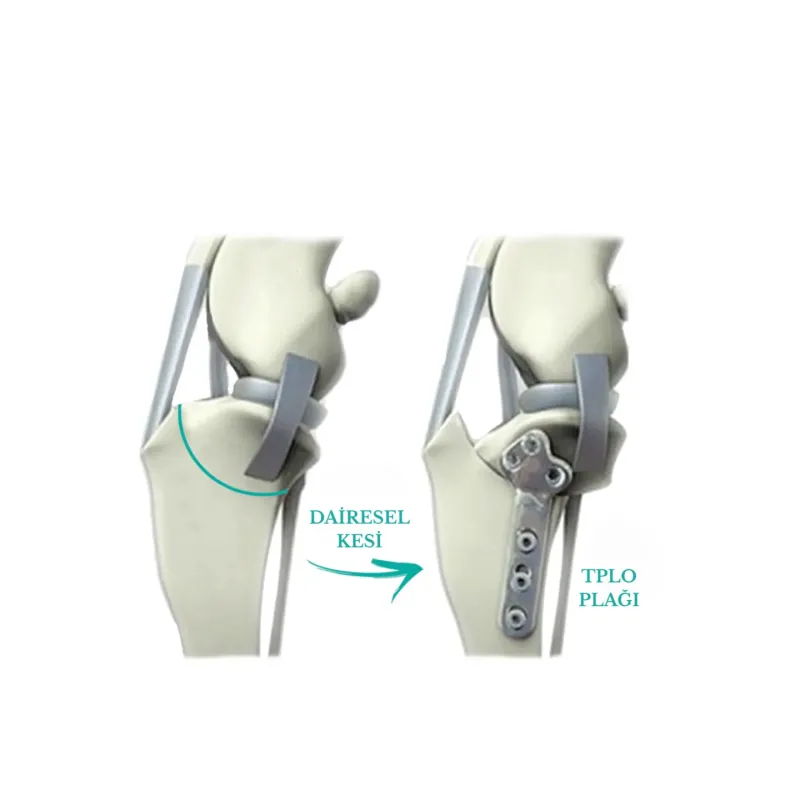

Bu ameliyatlar, diz ekleminin biyomekaniğini ve geometrisini, stabiliteyi korumak için ön çapraz bağa gerek kalmayacak şekilde değiştirir. Teknikte, kemiği keserek ve yeni bir pozisyonda sabitleyerek kaval kemiğinin üst kısmının yeniden şekillendirilmesini içeren birkaç varyasyon vardır. Medicapet olarak bu tekniklerin tümünü gerçekleştiriyor olabilmekle birlikte, yapılan bilimsel çalışmalar ışığında uzun vadede en sağlıklı teknikler olarak sunulan TTA ve TPLO cerrahilerini uygulamayı tercih ediyoruz.

Bu ameliyat, tibianın üst kısmında dairesel bir kesi oluşturulmasını ve kemikteki önceki eğim artık mevcut olmayana kadar plato segmentinin döndürülmesini içerir. Daha sonra kemik, kemik plakası ve vidalar kullanılarak bu yeni pozisyonda sabitlenir. Böylece femurun tibia üzerinde uygunsuz şekilde kayması engellenmiş olur. Hassas ölçümler ve kusursuz el maniplasyonu gerektirdiği için tecrübeli ve ehil cerrahlar tarafından uygulanmalıdır.

Kemik iyileşmesinin bağ iyileşmesinden daha kolay ve hızlı olması sebebiyle, bu onarımlar hasarlı bağın değiştirilmesi için tasarlanan ameliyatlardan önemli ölçüde daha sağlamdır. En büyük pratik fayda, tüm köpeklerin 1-3 gün içinde ameliyat edilen uzuvda ağırlık taşımaya başlamasının beklenmesiyle, uzuv kullanımının çok güvenilir bir şekilde geri dönmesidir. TPLO ve TTA'nın mekanik avantajları, hızlı işleve dönüşle birleştiğinde, özellikle ağır köpekler, atletik hayvanlar, hafif aksama

gösteren hayvanlar ve her iki diz eklemini de etkileyen ön çapraz bağ yaralanmaları olan hayvanlar için önemlidir. Her iki dizini aynı anda etkileyen ön çapraz bağ yaralanmaları olan bazı hayvanlarda, TPLO tek bir ameliyatta her iki diz eklemine uygulanabilir. Bağ değiştirme teknikleri kullanıldığında bu mümkün değildir.

Köpeklerin %90'ından fazlası TPLO veya TTA'dan sonra normal aktivitelerine döner. Hatta her iki tekniği kedilere de başarıyla uygulayabiliyoruz. Bu operasyonlardan sonra kedi ve köpeklerin devam eden ilaç tedavilerine gerek kalmadan sınırlandırılmamış egzersize dönmelerini bekliyoruz. TPLO ve TTA için başarı oranları birbirine çok benzerdir.